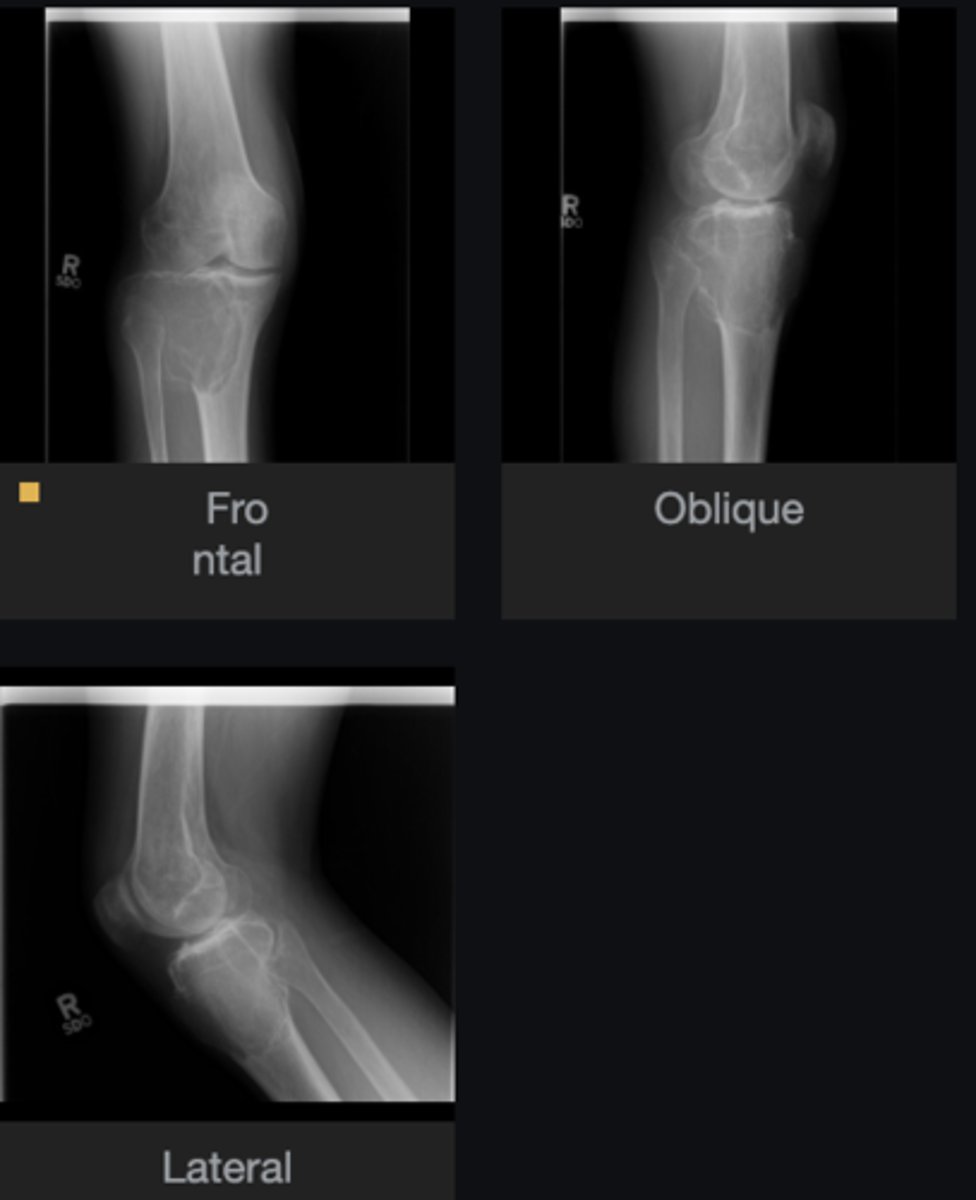

- Ulna

- Diaphysis

- Sclerotic

- Small, lucent nidus (< 1cm) in the cortex

- Geographic)

- Cortical thickening

Describe the lesion

<p>Describe the lesion</p>

Osteoid osteoma

Most likely diagnosis?

<p>Most likely diagnosis?</p>

Severe pain (worse at night, relieved by aspirin)

What is the hallmark history of a patient with this lesion?

<p>What is the hallmark history of a patient with this lesion?</p>

- Refer to orthopedist

- Adjust spine

Next step?

<p>Next step?</p>

None

Concerns/complications?

<p>Concerns/complications?</p>